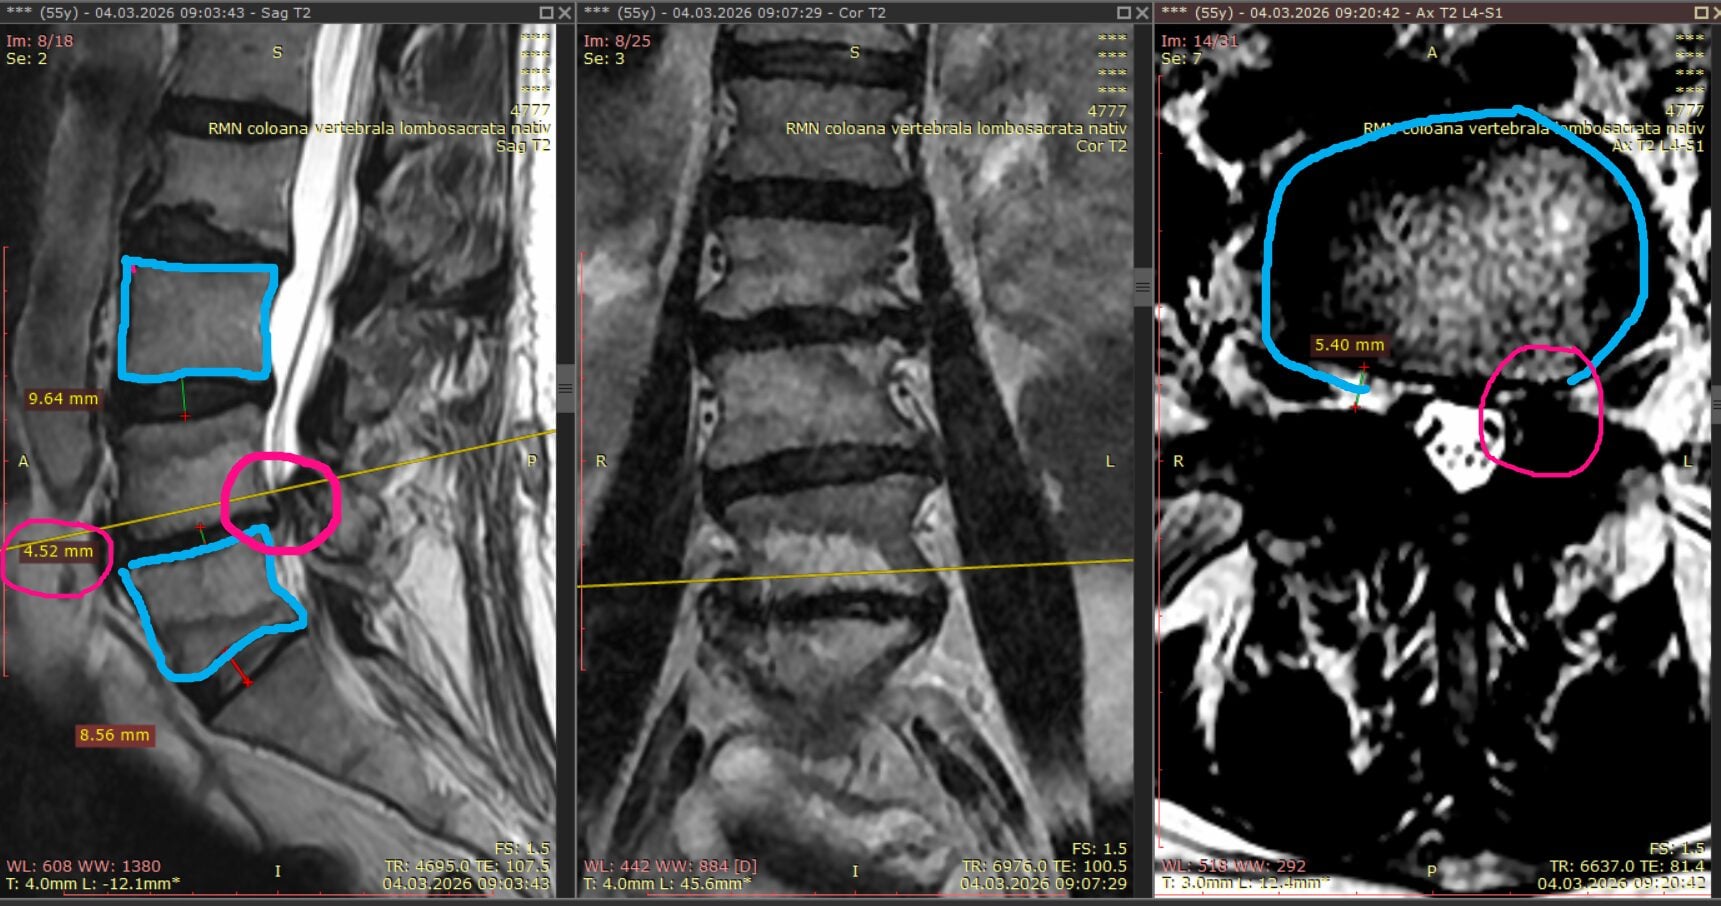

Examinarea RMN a coloanei lombare a evidențiat modificări structurale importante la nivelul discului L4-L5.

În imaginea laterală se observă:

• corpurile vertebrale,

• spațiile intervertebrale, în special segmentul L4-L5.

Înălțimea discului L4-L5 era de doar 4,5 mm, comparativ cu discurile supraiacente, care prezentau valori de aproximativ 9,6 mm și 8,5 mm. Această diferență indică o degenerare avansată și o compresie semnificativă a discului afectat.

Discul fusese deja compromis de hernia inițială și de intervențiile chirurgicale anterioare, iar peretele discal nu mai putea reține eficient nucleul gelatinos, favorizând apariția unei noi hernii.

RMN-ul a evidențiat și o compresie importantă pe partea stângă, exact în zona operată anterior, confirmând diagnosticul de recidivă de hernie de disc L4-L5.